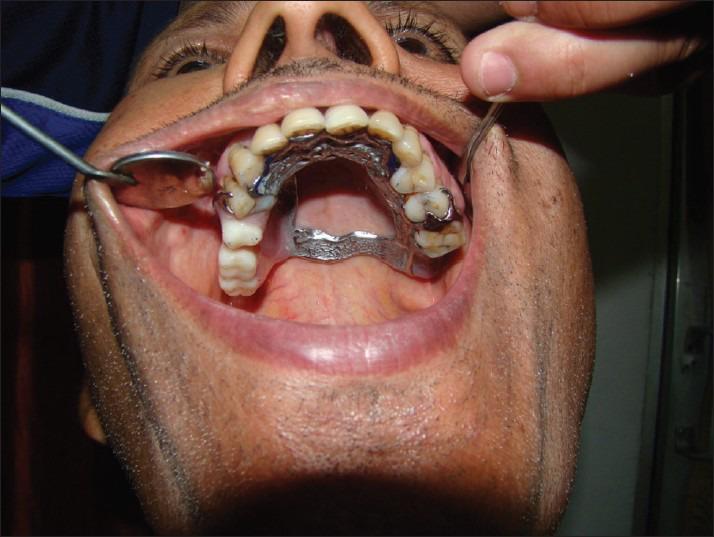

Rehabilitation of hemimaxillectomy patients can be challenging. The most common problem with prosthetic treatment in such patients is in getting adequate retention, stability, and support. The size and location of the defect usually influences the amount of impairment and difficulty in prosthetic rehabilitation. The obturator prosthesis is commonly used as an effective means for rehabilitating hemimaxillectomy cases. In cases of large maxillary defects, movement of the obturator prosthesis is inevitable and requires a form of indirect retention to limit the rotation of the prosthesis. The goal of prosthodontics is rehabilitation of missing oral and extraoral structures along with restoration of the normal functions of mastication, speech, swallowing, appearance, and so on. Malignancies are common in the oral region, which are treated through surgical intervention. Surgical intervention creates communication between the oral cavity, nasal cavity, and maxillary sinus. In such cases, it is very difficult for the patient to perform various normal functions like mastication, swallowing, speaking, and so on. Prosthodontic rehabilitation with obturator prosthesis restores the missing structures and acts as a barrier between the communication among the various cavities.

半侧上颌骨切除患者的康复治疗具有挑战性。此类患者进行修复治疗时最常见的问题是获得足够的固位、稳定和支持。缺损的大小和位置通常会影响修复康复的受损程度和难度。阻塞器假体通常作为修复半侧上颌骨切除病例的有效手段。在上颌骨大缺损的病例中,阻塞器假体的移动不可避免,需要某种形式的间接固位来限制假体的旋转。口腔修复学的目标是修复缺失的口腔和口外结构,同时恢复咀嚼、言语、吞咽、外观等正常功能。口腔区域恶性肿瘤很常见,需通过手术干预进行治疗。手术干预会在口腔、鼻腔和上颌窦之间形成通道。在这种情况下,患者很难进行咀嚼、吞咽、说话等各种正常功能。使用阻塞器假体进行口腔修复可恢复缺失结构,并在各个腔隙之间的通道起到屏障作用。